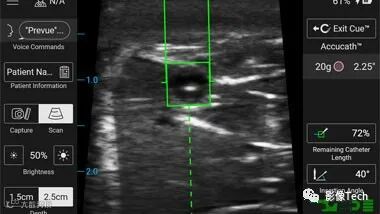

该系统包括集成可视化工具,例如 Cue™ 针头跟踪系统,为护理人员提供连续、实时的针头位置跟踪,以及 Sherlock 3CG+™ 尖端确认系统,用于在置入导管或针头后,通过影像技术确保其准确位置和定位。

SiteRite™ 9 超声系统集成了 Sherlock 3CG+™ 尖端确认系统(TCS),专用于血管通路,其可视化工具,可帮助医生在 PICC 手术期间识别和测量血管。

Cue™ 针头跟踪技术用于提供与目标结构相关的导针轨迹和针尖位置的视觉反馈。与“盲目”导管放置相比,实时可视化已被证明有助于减少医生尝试置入的次数,从而改善患者的超声引导针置入体验。